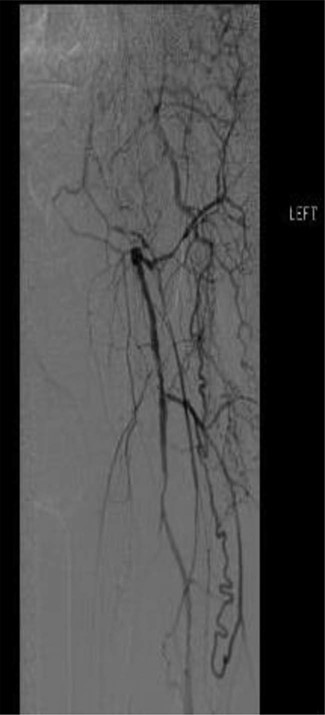

Workup began with noninvasive studies of the left lower extremity displaying aortoiliac occlusive disease and infrainguinal disease. Aortogram demonstrated a severely calcified aorta, patent left common iliac and proximal hypogastric arteries, with occlusion of the left external iliac, left common femoral and left superficial femoral arteries (Fig. 1). The right iliac system was patent apart from an occluded right hypogastric artery. A selective left lower extremity angiogram demonstrated reconstitution of the mid-to-distal profunda femoris artery (Fig. 2) to the proximal above-knee popliteal artery at the adductor hiatus (Fig. 3). Extensive collateralization was appreciated in the pelvis and lower extremity, between the residual left hypogastric artery and profunda femoris artery. Endovascular revascularization attempts were unsuccessful.

Selective left lower extremity angiogram demonstrating reconstitution of the above-knee popliteal artery at the adductor canal